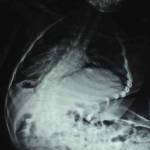

Funcionalidad y calidad de vida luego de la cirugía de escoliosis neuromuscular

Patricia C. Curbelo Nova, Claudio Silveri, Alejandro Cuneo, Rodrigo Olivera